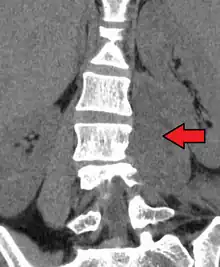

Psoas abscess

Paraspinal abscess in the psoas muscle

Psoas abscess is a collection of pus in the iliopsoas muscle compartment.[1][2] It can be classified into primary psoas abscess (caused by hematogenous or lymphatic spread of a pathogen) and secondary psoas abscess (resulting from contiguous spread from an adjacent infectious focus).[2]

Psoas abscess may be caused by lumbar tuberculosis. Owing to the proximal attachments of the iliopsoas, such an abscess may drain inferiorly into the upper medial thigh and present as a swelling in the region. The sheath of the muscle arises from the lumbar vertebrae and the intervertebral discs between the vertebrae. The disc is more susceptible to infection, from tuberculosis and Salmonella discitis. The infection can spread into the psoas muscle sheath.[3]